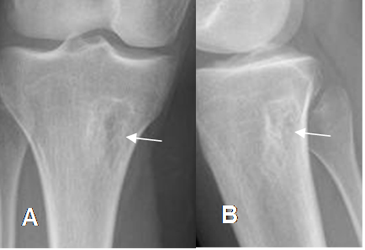

Fig 95. Defecto fibroso cortical.

Rx AP. Imagen lítica, de bordes bien definidos y escleróticos, por defecto fibroso cortical.